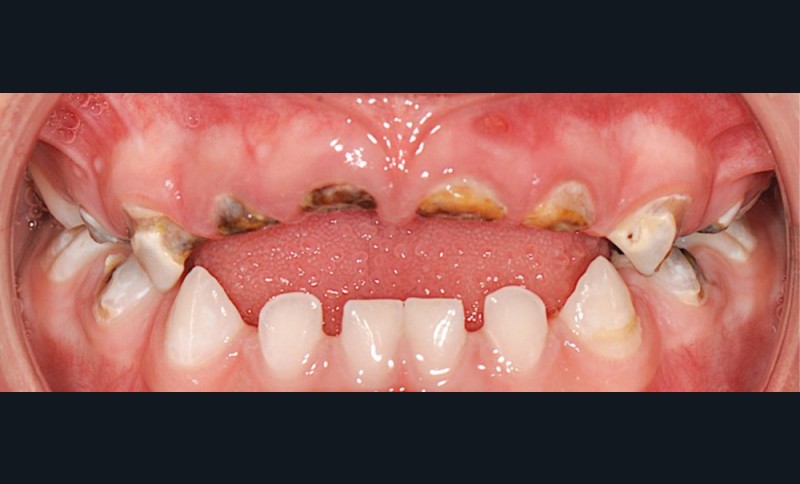

L’OMS recommande un allaitement exclusif jusqu’à l’âge de 6 mois, et associé à d’autres aliments jusqu’à 24 mois [3]. S’il n’est plus nécessaire de démontrer les bienfaits de l’allaitement sur la santé globale de l’enfant, il reste néanmoins utile d’en prévenir certaines pratiques parfois inadaptées pouvant conduire à l’apparition de carie de la petite enfance (CPE) (fig. 1 et 2). L’allaitement au sein exclusif pendant une période de 6 mois présente bien des avantages pour le nourrisson et la mère, et notamment celui de protéger contre les infections gastro-intestinales, aussi bien dans les pays en développement que dans les pays industrialisés. Par ailleurs, une mise au sein précoce, dans l’heure qui suit la naissance, réduit le taux de mortalité.

Les études soulignent également les bienfaits de l’allaitement sur la santé orale : il favorise notamment le développement de la musculature, la croissance maxillo-faciale et limite les malocclusions chez l’enfant [4]. Si la cariogénicité du lait maternel n’a pas été examinée de manière approfondie, des études suggèrent qu’elle est plus importante que celle du lait de vache, mais moins importante que celle des préparations infantiles. Ceci est à considérer notamment lors de consommations fréquentes [5, 6]. Par conséquent, il a été mis en évidence que l’allaitement maternel pourrait être un facteur de protection contre la CPE jusqu’à l’âge de 12 mois. Pour autant, des pratiques d’allaitement à la demande, après l’éruption des dents temporaires, et notamment la nuit, associées à des pratiques de cosleeping (ou co-dodo : l’enfant dort avec la mère), contribueraient à développer la CPE après 12 mois [7, 8]. Si d’autres facteurs sont également à considérer dans le développement de la CPE [9], les études soulignent que l’allaitement prolongé [au-delà de 24 mois]…